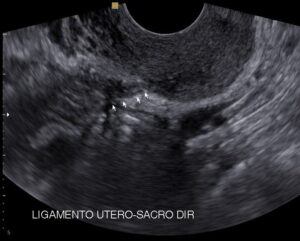

Exame de ultrassom transvaginal com preparo intestinal. Identifica-se endometriose profunda localizada no ligamento útero-sacro direito que encontra-se espessado. As setas brancas assinalam a endometriose.